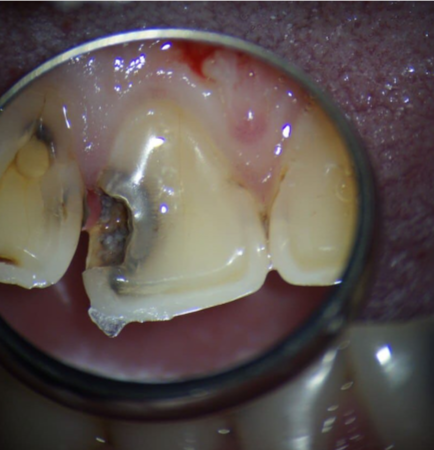

Сокольская Оксана Юрьевна: портфолио (2)